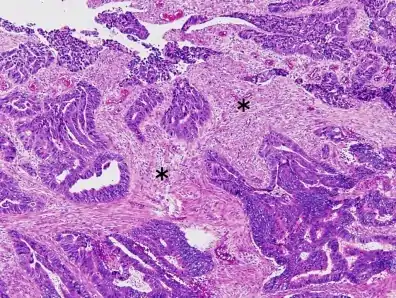

Colorectal carcinoma with desmoplastic reaction (*)

- Frequently desmoplasia

- Dirty necrosis, consisting of extensive central necrosis with granular eosinophilic karyorrhectic cell detritus.[6][7] It is located within the glandular lumina,[7] or often with a garland of cribriform glands in their vicinity.[6]